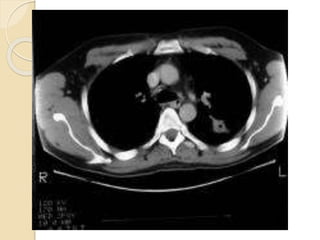

CT ABDOMEN:

Mildly enlarged liver with multiple variable

sized marginally enhanced cystic lesions

are seen scattered in both liver lobes

and caudate lobe . the largest measures

about 3.5 cm in diameter and located in

medial segment of the left liver lobe……

signs cobe with multiple liver

granulomas Normal enhancement of the

main portal vein and its two main

branches. No dilated intra-hepatic biliary

CT ABDOMEN: Mildly enlargedliver with multiple variable sized marginally enhanced cystic lesions are seen scattered in both liver lobes and caudate lobe . the largest measures about 3.5 cm in diameter and located in medial segment of the left liver lobe…… signs cobe with multiple liver granulomas Normal enhancement of the main portal vein and its two main branches. No dilated intra-hepatic biliary